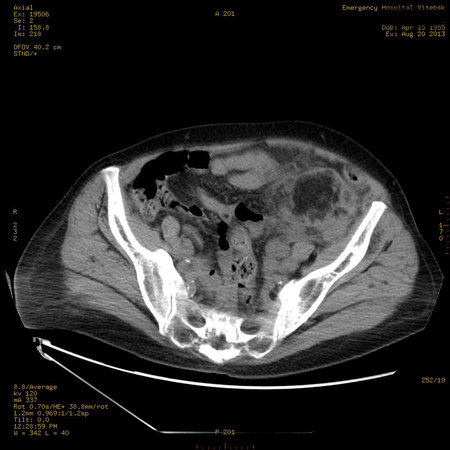

УЗИ почек - туберозный склероз

Пожилая женщина с нормальными мочевиной и креатинином.

Ангиомиолипоматоз почек , думаю компонент туберозного склероза.

Да, туберозный склероз.

Случай консультирован на кафедре радиологии Католического университета г.Лёвен (Бельгия) - зав каф. профессор Р.Оуен.